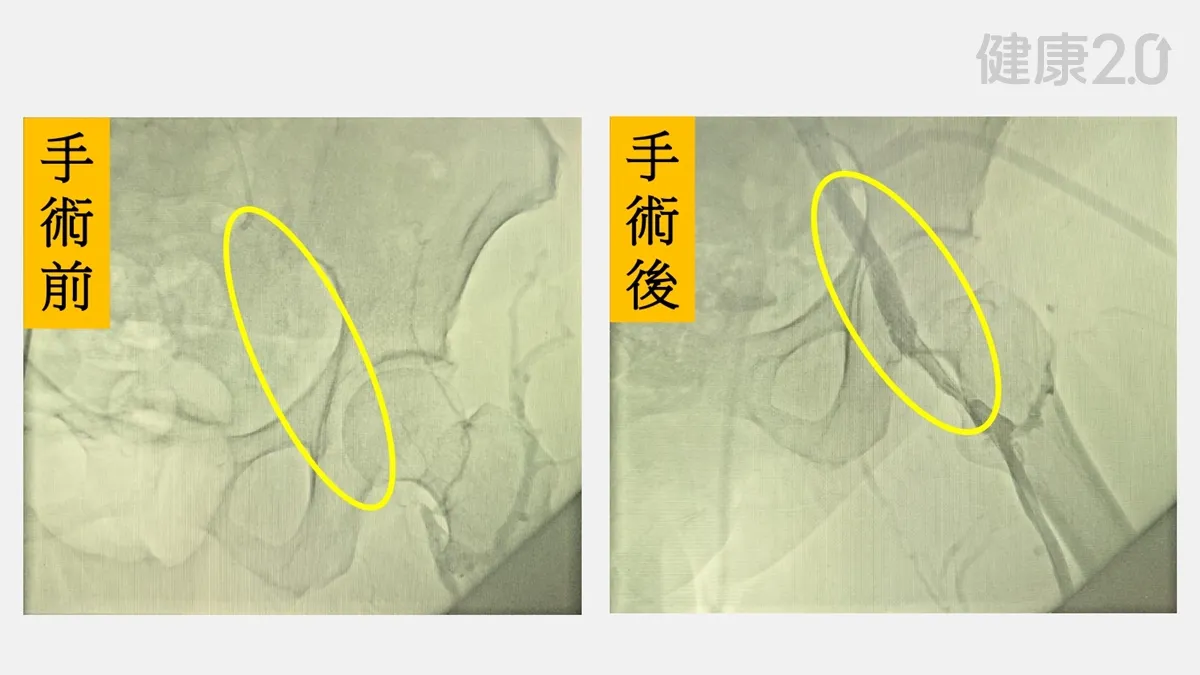

髖部腫痛不是關節退化 竟藏致命危機!7旬婦「髂靜脈壓迫」嚴重恐肺栓塞